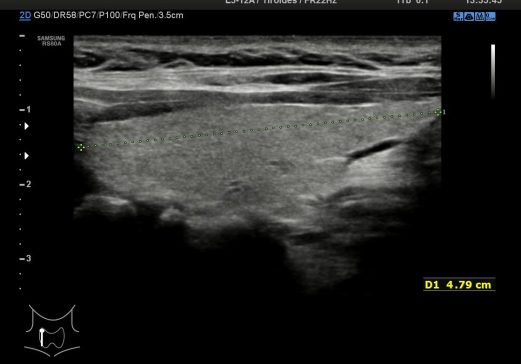

5. Medida LD Longitudinal

La 5 es la foto correspondiente a la medida en Longitudinal del LD. Es vital sacar todo el Tiroides en longitudinal para poder medirlo en toda su extensión en este corte,tanto LD como LI.(Luz Noemí).

The 5 is the photo corresponding to the measure in Longitudinal of the LD. It is vital to remove the entire Thyroid in longitudinal to be able to measure it in its entirety in this section, both LD and LI